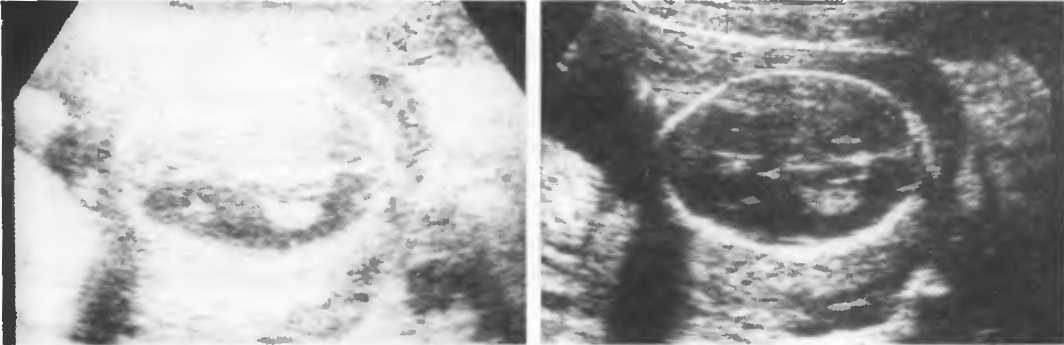

Рис.8б. Два аксиальных среза головки плода, развернутые на 180°. Перед проведением исследования ориентация изображения на экране должна быть проверена, как показано на рис. 8а.

Рис. 13г. Головка плода. Слева: общая чувствительность слишком высока. Справа: общая чувствительность определена правильно, однако она слишком высока для точного измерения бипариетального диаметра.

Рис. 13д. Общая чувствительность слишком низка для исследования внутренней зхоструктуры, но достаточна для точного измерения бипариетального диаметра.

Рис.13е. Слева: плохая визуализация в результате слишком высокого усиления передних отделов; сравните нечеткое изображение передней части головки с достаточно четким изображением задних отделов (сравните рис. 13ги 13д;. Справа: регулировка по глубине была изменена; теперь определяется слишком низкое усиление близких структур и слишком высокое усиление глубокорасположенных структур.